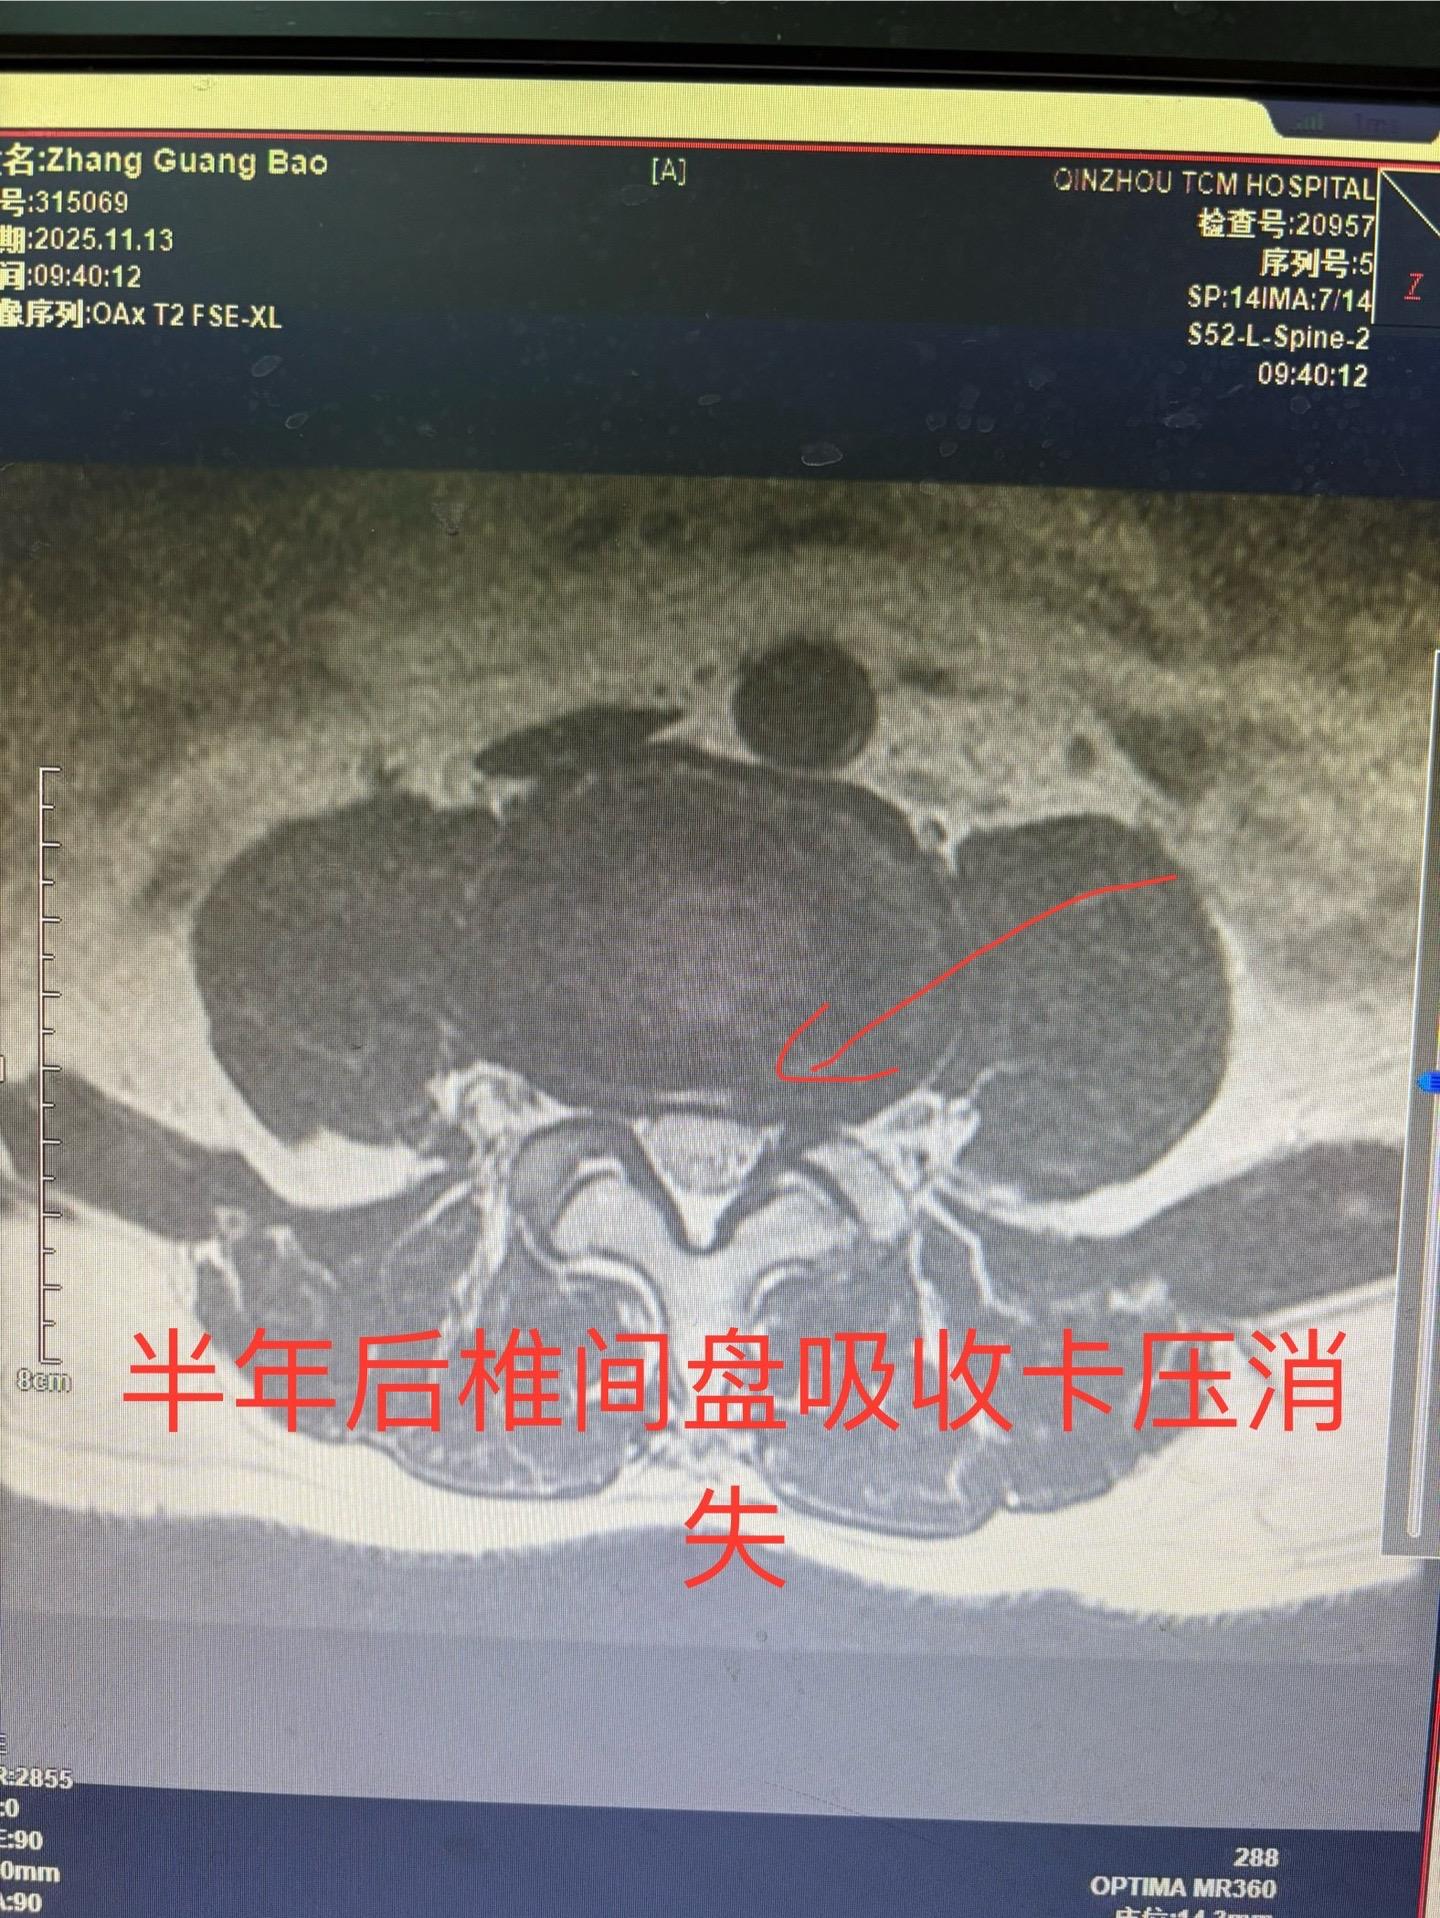

前段时间发现一例椎间盘突出病人保守治疗突出自行吸收,最近又发现一例治疗半年椎间盘突出已自行吸收,证明这不是个例。有部分人确实可以自行吸收,人的人体是很神奇的